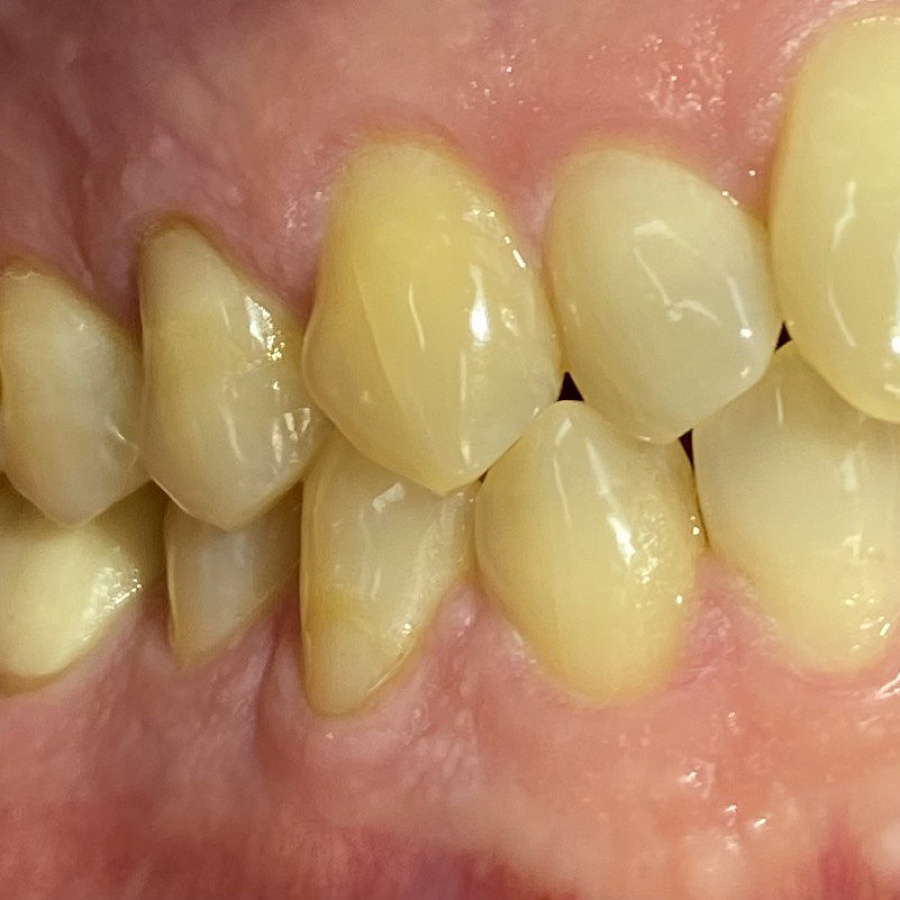

Пациент обратился с жалобами на неровные передние зубы верхней и нижней челюстей.

сужение зубных рядов,

обратное перекрытие в области фронтальных зубов слева,

разворот по оси передних зубов верхней и нижней челюстей,

стираемость эмали зубов,

индивидуальную микродентию 12 и 22 зубов.

Ортодонтическое лечение с помощью элайнеров длилось 10 месяцев. Далее последовало протезирование и установка виниров.

Результат лечения